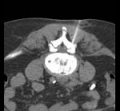

Under computer tomographic or magnetic resonance imaging control, drugs are injected with millimeter precision into the neuralgic points of the spine using fine injection needles. In many patients, this can result in significant pain relief or even freedom from pain. All pain therapy treatments can be carried out on an outpatient basis without any problems due to the low complication rates. A treatment takes a maximum of 10 to 30 minutes.

Periradicular therapy (PRT) is used as a pain therapy procedure for a herniated disc, but also for other back disorders. Here, painkilling and anti-inflammatory drugs are injected with millimeter precision into the painful nerve root under computer or magnetic resonance imaging control. Corticosteroids and long-acting local anesthetics are used. The corticosteroids reduce the swelling of the irritated nerve root, while the local anesthetics reduce the local radiation of pain.

These interventions are CT-assisted, in which a thin special needle is positioned directly on the corresponding nerve plexus (neck, thorax, abdomen, or pelvis) under local anesthesia, and a mixture of local anesthetic and highly concentrated alcohol solution is injected locally. The alcohol solution leads to chemical obliteration of the nerve plexus and thus to pain reduction. The local anesthetic leads to immediate pain reduction when indicated and performed correctly and thus has diagnostic value. For this reason, the procedure is often performed in two stages.